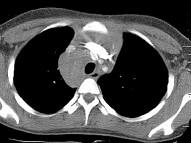

7岁,男,发热、消瘦,数月前触及颈部淋巴结肿大,CT和MR检查如图,请选择最可能的诊断 ( )A.淋巴瘤B.结节病C.淋巴结核...

问题 7岁,男,发热、消瘦,数月前触及颈部淋巴结肿大,CT和MR检查如图,请选择最可能的诊断 ( )

选项 A.淋巴瘤 B.结节病 C.淋巴结核 D.转移性淋巴肿大 E.胸腺瘤

答案 A